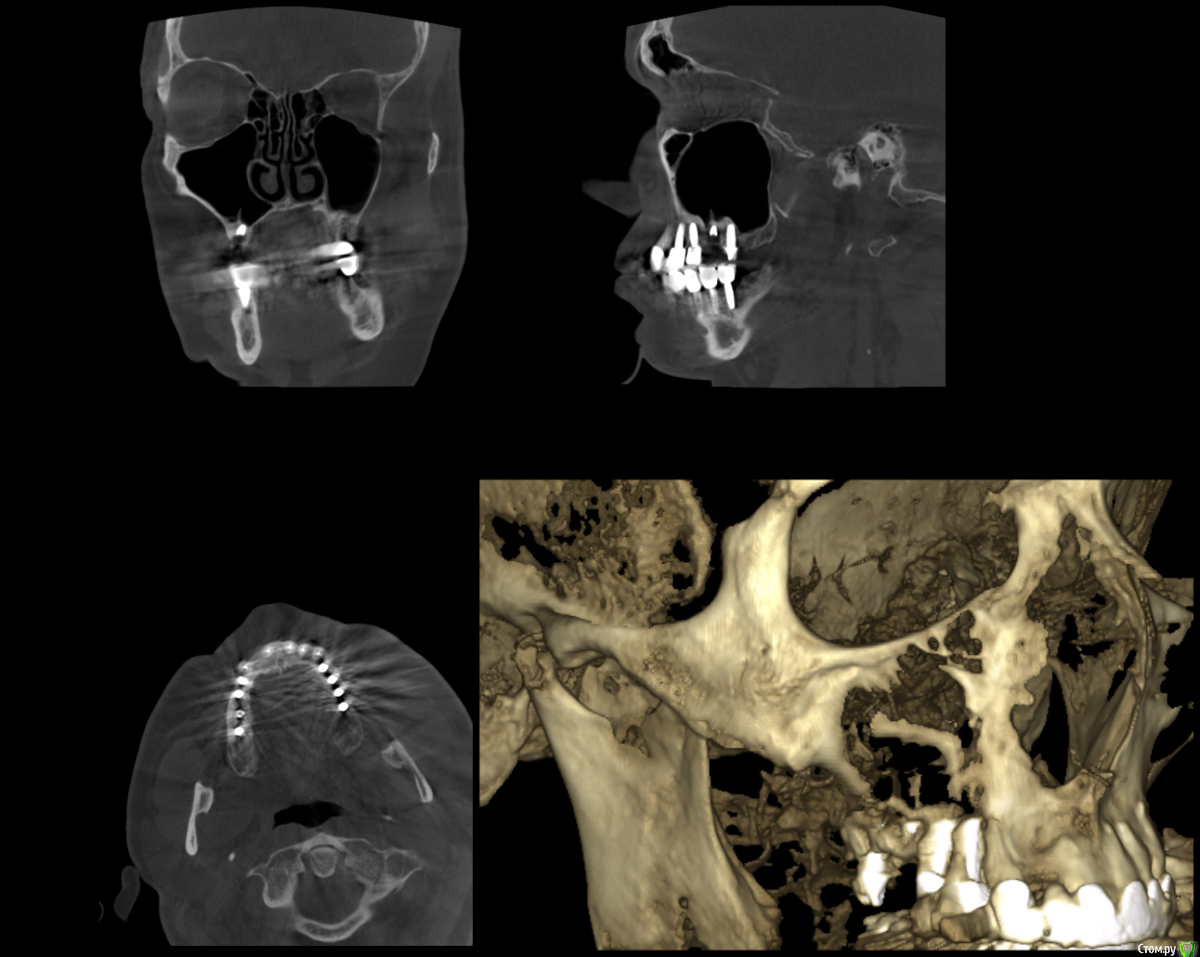

Alex1964 Опубликовано 12 января, 2021 Автор Поделиться Опубликовано 12 января, 2021 Покажите снимокСнимка нет, есть КТ, но оно же большое...Вот скриншот из КТ: КТ в программе Romexis_Viewer, могу выложить файлы из папки images (dcm и txt, это же, как я понимаю, и есть сама КТ?)Или могу выложить всю папку КТ (то есть весь CD-диск)Подскажите, как правильно, сделаю.All_2.txt Ссылка на комментарий